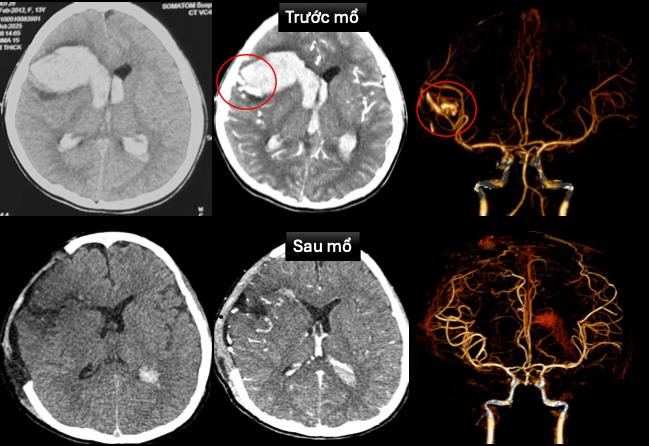

Tại đây, các bác sĩ ghi nhận bé T. hôn mê sâu, thở máy qua nội khí quản, nhịp chậm, huyết áp thấp đang duy trì thuốc vận mạch. Bệnh nhân được siêu âm tim, chụp cắt lớp vi tính sọ não dựng hình mạch máu não cấp cứu, và chẩn đoán dị dạng động tĩnh mạch trán phải vỡ gây xuất huyết nhu mô não, lan vào hệ thống não thất, sốc tim, rối loạn nhịp, bệnh cơ tim xốp.

Hình ảnh chụp cắt lớp vi tính sọ não, dựng hình mạch máu não trước và sau mổ  của bé T., ảnh BV Nhi Đồng 1

Hình ảnh chụp cắt lớp vi tính sọ não, dựng hình mạch máu não trước và sau mổ của bé T. Ảnh: BV Nhi Đồng 1

Đến nay, sức khỏe của bé đã dần ổn định, bé tỉnh táo, còn yếu nhẹ chân phải, đã được rút máy tạo nhịp tim và ngưng thuốc vận mạch. Chẩn đoán hình ảnh sau mổ không còn ghi nhận dị dạng mạch máu não, bệnh cơ tim xốp cải thiện.